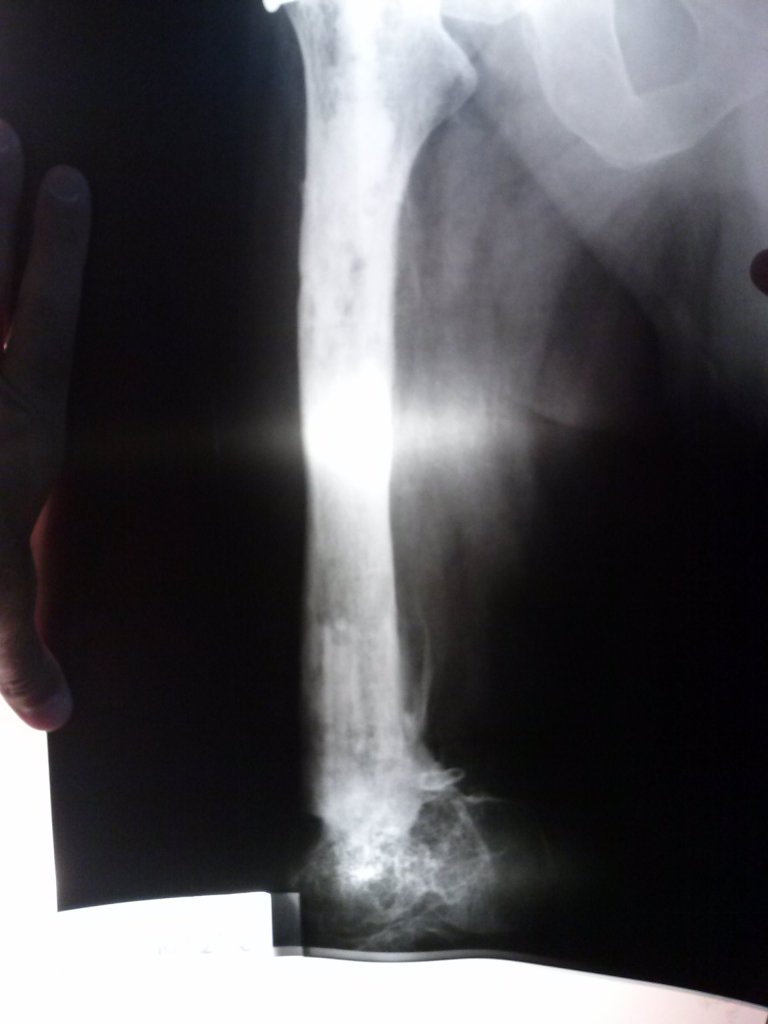

Infección y deformidad en tobillo y pie mas acortamiento óseo de pierna

Luego de varios años y cirugías sufridas por un accidente en moto, mi pie y pierna presentaban una gran deformidad asociada a una osteomielitis .

En mi provincia Chubut no podían tratarme más y solo me ofrecían la amputación

Tras viajar a BS AS y tener una consulta personal con el Dr Dratewka y Equipo en Cotram me realizaron estudios de imágenes y explicaron las posibilidades de Reconstrucción y evitar así la amputación

No solo trataron mi infección sino que corrigieron mi pie y me alargaron la pierna para poder caminar sin dificultades